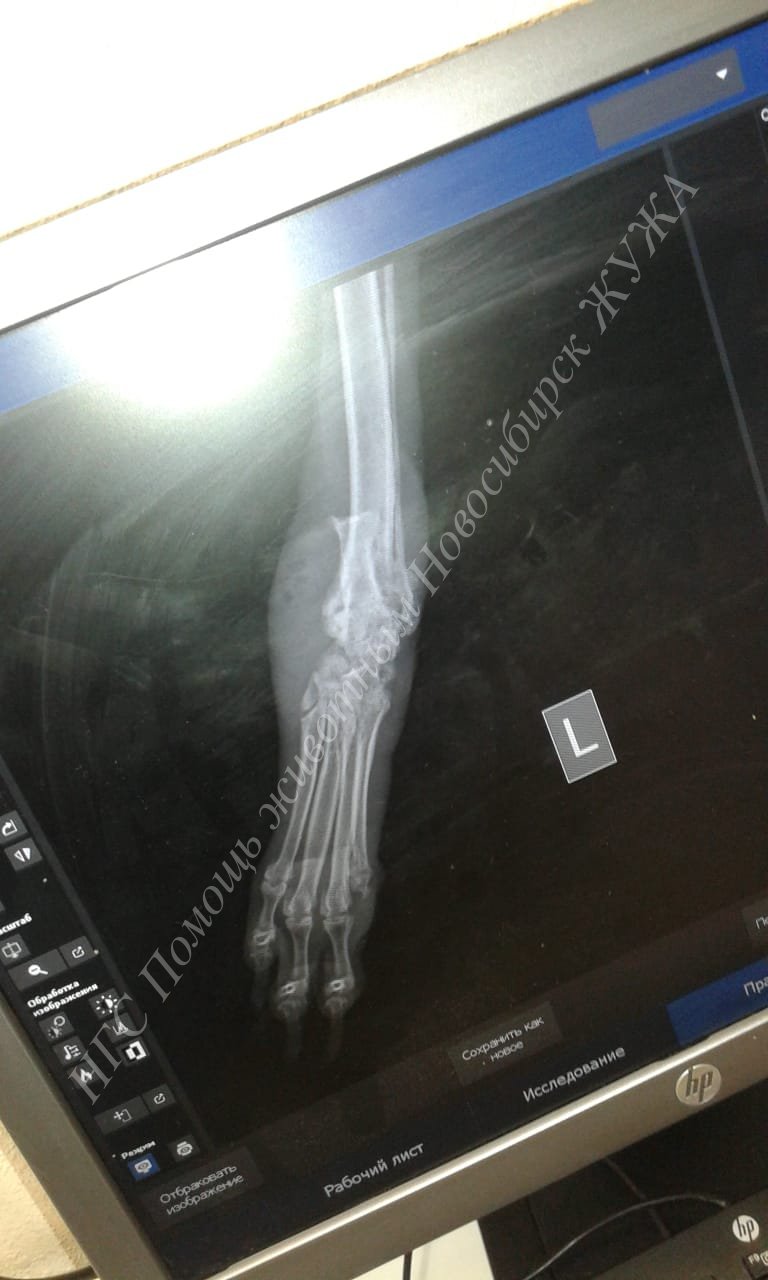

Вчера мы с Жуженькой стриглись, и ездили в Ветлекарь, у нашей девоньки большая и серьёзная проблема с пролежнем на задней лапке, он стал больше буквально за несколько дней, сустав опух и видно кость, выглядит всё очень страшно. Я так корю себя, что не бросила все проблемы в приюте у нас и не поехала с ней в клинику раньше.

У Жуженьки прям до кости всё оголилось, я когда увидела, мне стало плохо, врач сказала, что остеомиелита пока нет, но он возможен. У Жужи паталогическая подвижность сустава в этом месте, и выскочила косточка, хрящ воспалён, т.е. возник гнойный артрит и из сустава вытекает синовиальная жидкость.

Прописали очень сильную дозу Амоксиклава, чтоб он проник в кость, я купила аналог, и вот мазь, которую нам ещё в клинике заложили, она 500р стоит тюбик, взяла сразу в клинике. Нужно прям обильно мазать и делать перевязки, особым способом бинтовать, своего рода кокон вокруг лапки, прям много много бинта, 2 рулона уходит за раз. В день делать 2 перевязки.

Врач сказал, что если не будет положительной динамики в течении недели, то лапку надо ампутировать

, я когда это услышала, в глазах потемнело. Я очень хочу спасти лапу!

Вчера потратила на рентген, перевязки, приём и гель 3000руб., + 1100руб. на стрижку, и сегодня ещё купила на 713руб. лекарств и бинтов стерильных, которые будут к ране примыкать, и не стерильных, сверху обвязывать кокон.